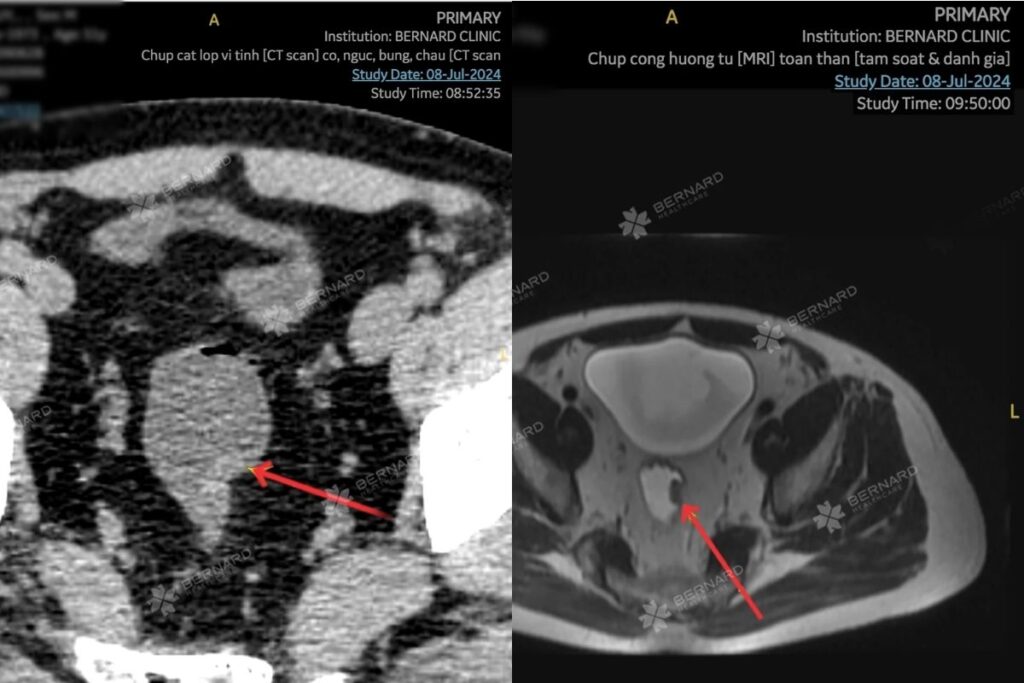

Theo quy trình 9 trạm Ningen Dock tại Bernard, nam khách hàng được tầm soát chuyên sâu các loại ung thư phổ biến bằng công nghệ cao CT Scan và MRI.

Kết quả chụp CT Scan phát hiện bất thường tại vùng bụng – chậu. Cụ thể: Có một cấu trúc có đậm độ trung bình, lồi vào lòng bên trái (T) trực tràng cao gây khuyết lõm, đường kính (d) 7x15mm.

Đi kèm trong gói khám, kết quả MRI toàn thân nhằm tìm kiếm dấu chứng ung thư ở các tạng, cơ quan khác trong cơ thể, cũng ghi nhận tổn thương tương tự tại vị trí bên trái trực tràng cao, với đường kính khoảng 7x15mm, không rõ dấu hiệu hạn chế khuếch tán.